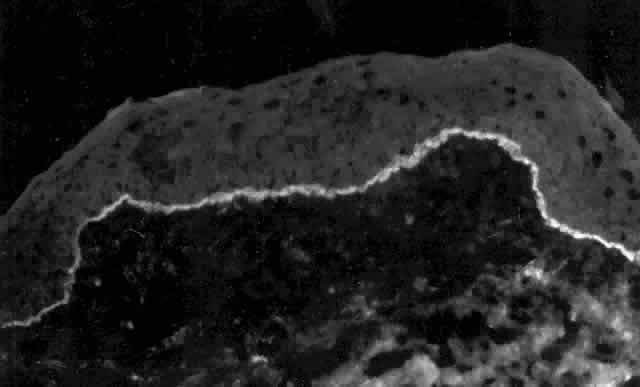

Pemphigus can be differentiated from bullous pemphigoid and from cicatricial pemphigoid on histologic and immunologic bases. Whereas the bullae in pemphigus are intraepidermal, those occurring in bullous pemphigoid and in cicatricial pemphigoid are subepidermal, between epidermis and dermis, or between mucosa and submucosa. Acantholysis is not present in the latter two conditions.5 In bullous pemphigoid and in cicatricial pemphigoid there are tissue-fixed immunoglobulins in the subepidermal basement membrane zone (Fig. 2).11 This is in contrast to the interepidermal fixation of antibodies (Fig. 3) seen in pemphigus (Table 1).

Fig. 2. Fluorescence microscopy of conjunctiva from a patient with cicatricial pemphigoid affecting the eye. The antibody used was a fluorescein-conjugated antibody directed against human IgG. Note the bright, continuous, linear deposition of IgG at the epithelial basement membrane zone, a finding virtually diagnostic of cicatricial pemphigoid.

Fig. 3. Immunofluorescence microscopy of conjunctiva from a patient with pemphigus vulgaris. The antibody is a fluorescein-conjugated antibody directed against human IgG. Note the bright staining of the intercellular cement, brightly outlining the borders of all of the epithelial cells.